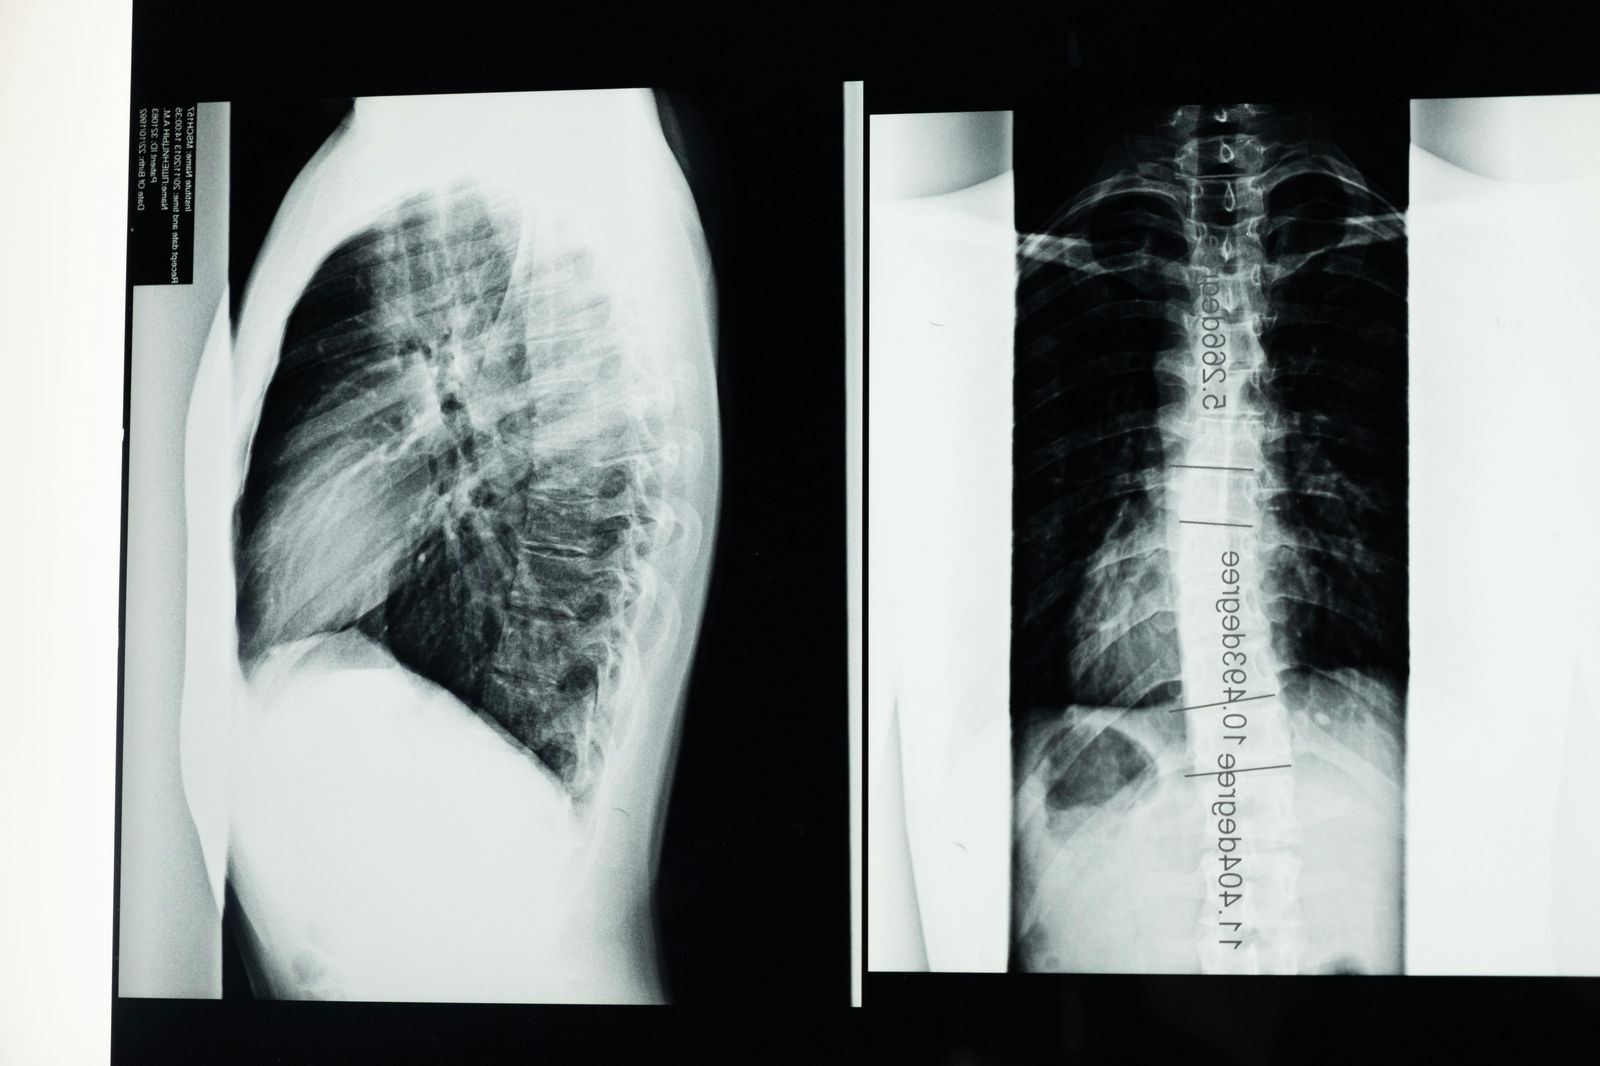

Radiografía columna vertebral.